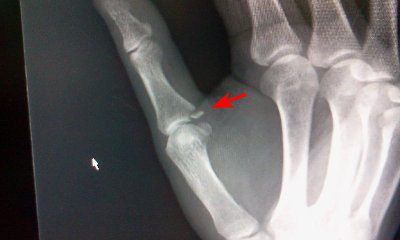

●右手親指の骨折

関節の広がっているところが欠損するように骨折。

関節可動部には影響は無いだろう。

ただし、骨折した骨片がかなり離れてしまっているので、遊離骨片化すると思われる。 |

| 矢印の部分の小さな骨片が骨折した部分。 |